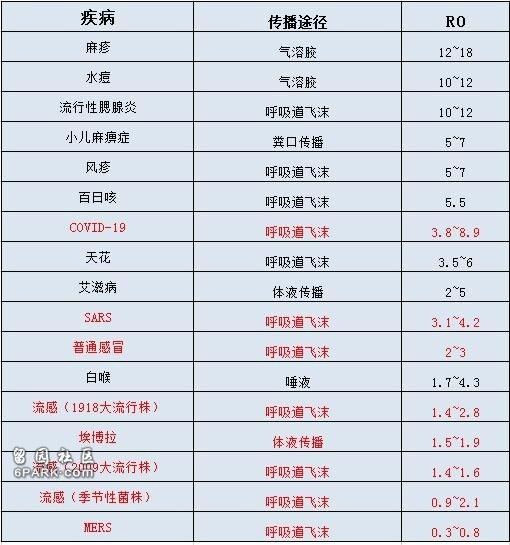

新冠病毒生存逆天还体现在传染性强上。在谈到某种疾病的传染性时,R0是一个绕不开的数值。在经典传染病学模型中,R0值常用来描述疫情的传染速率,可以反映出传染病暴发的潜力和严重程度。

R0指的是基本传染数或基本再生数(Basic Reproduction Number),表示在没有外力介入和所有人都没有免疫力的情况下,一个病例进入到易感人群中,在理想条件下可感染的二代病例个数。

如果R0大于1,那么这种传染病会以指数级散布,成为流行病,传遍整个人群;若R0小于1,则趋于消失;若R0等于1,传染病会变成人口中的地方性流行病。

总之,R0的数字愈大,代表流行病的控制愈难。

那么,新冠病毒的R0是多少呢?其实随着研究的不断深入,新冠肺炎的R0值一直在不断调整。1月份《新英格兰医学杂志》一项针对武汉最早确诊新冠肺炎患者的分析,R0值为2.2,即一名患者可以传染2.2人。

2月份医学预印本上medRxiv针对8866个病例进行的大规模临床回顾研究得出R0约为3.77的结论,这时,一名患者能传染3.77人。

4月份美国疾病管制局期刊《新发传染病》上最新研究再次上调这一数值,提出R0中值为5.7(95%CI 3.8–8.9),意味着一名新冠患者可以传染5.7人,是1月份所认为的2-3倍。

当R0为5.7时,至少82%的人口必须通过疫苗接种或事先感染才能获得免疫,由此产生群体免疫来阻止其传播,但这种代价太大了。

与其它疾病相比,新冠肺炎的R0值在一个什么水平呢?根据下列维基百科的一张图,不难看出,与SARS、MERS、埃博拉这些耳熟能详的传染病相比,此次新冠肺炎的基本传染数是最高的。